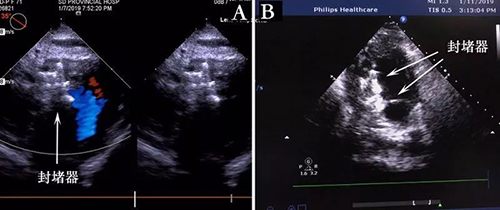

在麻醉科的鼎力配合下,李红昕和王正军两位医生配合,采用胸部小切口,首次经右心室膈面穿刺进行操作(图4)。术中他们克服了现有封堵器不够大,单枚封堵器不能完全封堵的困难,在经食管超声引导下,用两枚封堵器成功堵住了室间隔穿孔(图5)。患者转危为安,迅速康复。

图4

图5